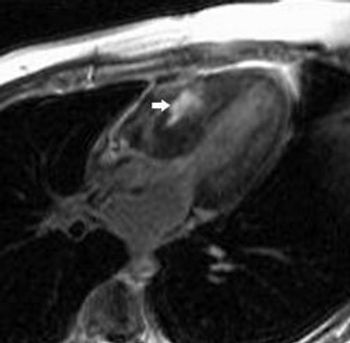

In this case, we examine a 49-year-old man with widespread metastatic sclerotic bone lesions. What is your diagnosis?